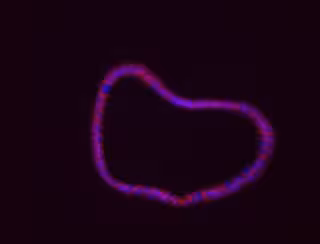

Organoide de colon generado a partir de tumores de ratón.

Organoide de colon generado a partir de tumores de ratón. - PILAR FAJARDO / CNB-CSIC

Cuenda y Juan José Sanz-Ezquerro, investigador del CNB-CSIC, apuntan que el abordaje en esta investigación ha sido "integral". "Pues hemos utilizado muestras humanas de plasma sanguíneo, se han analizado diferentes bases de datos de ARNm de pacientes humanos y hemos generado órganos miniaturizados u organoides derivados de tumores de pacientes, en colaboración con un equipo del Instituto de Investigaciones Biomédicas Alberto Sols (IIB-CSIC-UAM)", añaden.